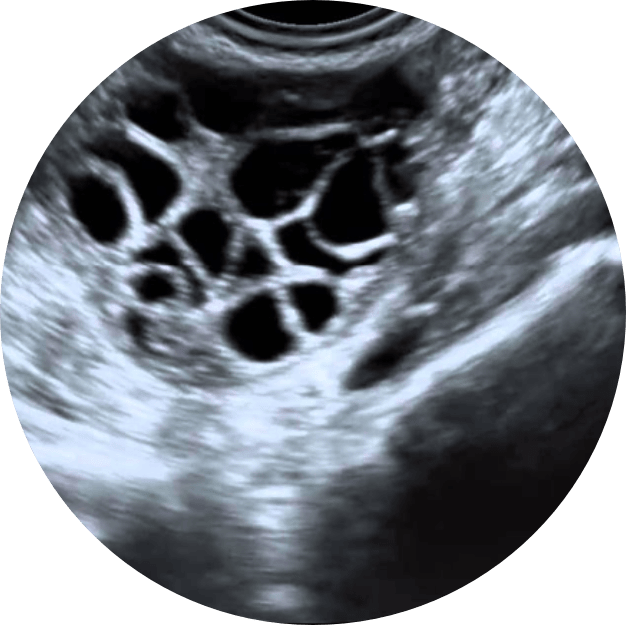

El síndrome de ovario poliquístico (SOP) es un trastorno hormonal común en mujeres en edad reproductiva que afecta la función de los ovarios. Las mujeres con SOP suelen tener desequilibrios hormonales, problemas de ovulación y, a menudo, pequeños quistes en los ovarios. El SOP puede influir en la fertilidad y está relacionado con un mayor riesgo de desarrollar problemas metabólicos y cardiovasculares.